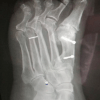

20 апреля 2021В Люберцах хирурги извлекли из ступни пациентки обломок металлической спицы Хирурги Люберецкой областной больницы провели успешную операцию по извлечению «блуждающего» обломка металлической спицы из ступни пациентки, сообщили в учреждении здравоохранения.